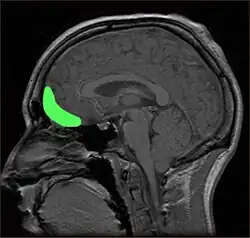

Um ästhetische Wahrnehmung mit bestimmten Gehirnarealen in Verbindung zu bringen, werden bildgebende Verfahren wie fMRT, EEG oder MEG eingesetzt, meistens während die Probanden Kunstwerke betrachten.[14][15] Dabei wird die neuronale Aktivität zwischen verschiedenen Bedingungen verglichen, etwa zwischen dem rein „pragmatischen“ Betrachten und der Betrachtung unter künstlerischen Gesichtspunkten,[5] zwischen verschiedenen Kunststilen[16] oder zwischen als schön oder hässlich bewerteten Bildern[16][17] oder geometrischen Formen[18]. Die in einer bestimmten Bedingung besonders aktiven Hirnregionen werden dann dem jeweiligen Aspekt als zugehörig angesehen.

Die Ergebnisse dieser Studie weisen weniger auf eine klar umrissene Hirnregion hin, die spezifisch für Kunstempfinden wäre, sondern eher auf ein hierarchisches Netzwerk solcher Regionen.[14] Zunächst sind die visuellen Areale unterschiedlich aktiv, je nachdem welche Art von Gemälde betrachtet wurde (abstrakte oder gegenständliche Malerei, Stillleben, Landschaftsgemälde oder Porträts).[16][17] Die Beurteilung eines Bildes als schön ging häufig mit der Aktivierung frontaler Areale einher, etwa dem orbitofrontalen Cortex,[16][18] dem Cortex cingularis anterior[16][17] und dem dorsolateralen[19] und ventralen[18] präfrontalen Cortex. Speziell der orbitofrontale Cortex wird auch allgemeiner mit der Beurteilung des Belohnungswerts eines Reizes in Verbindung gebracht.[20]

Des Weiteren wurden Aktivierungen von Arealen beschrieben, die mit Emotionen in Verbindungen gebracht werden (Amygdala, Inselrinde). Cinzia Di Dio und Vittorio Gallese[15] betonen zudem die Bedeutung motorischer Areale wie dem Prämotorcortex und den posterioren parietalen Cortex, insbesondere bei der Betrachtung von Statuen, die bestimmte Bewegungsposen zeigen.[21]